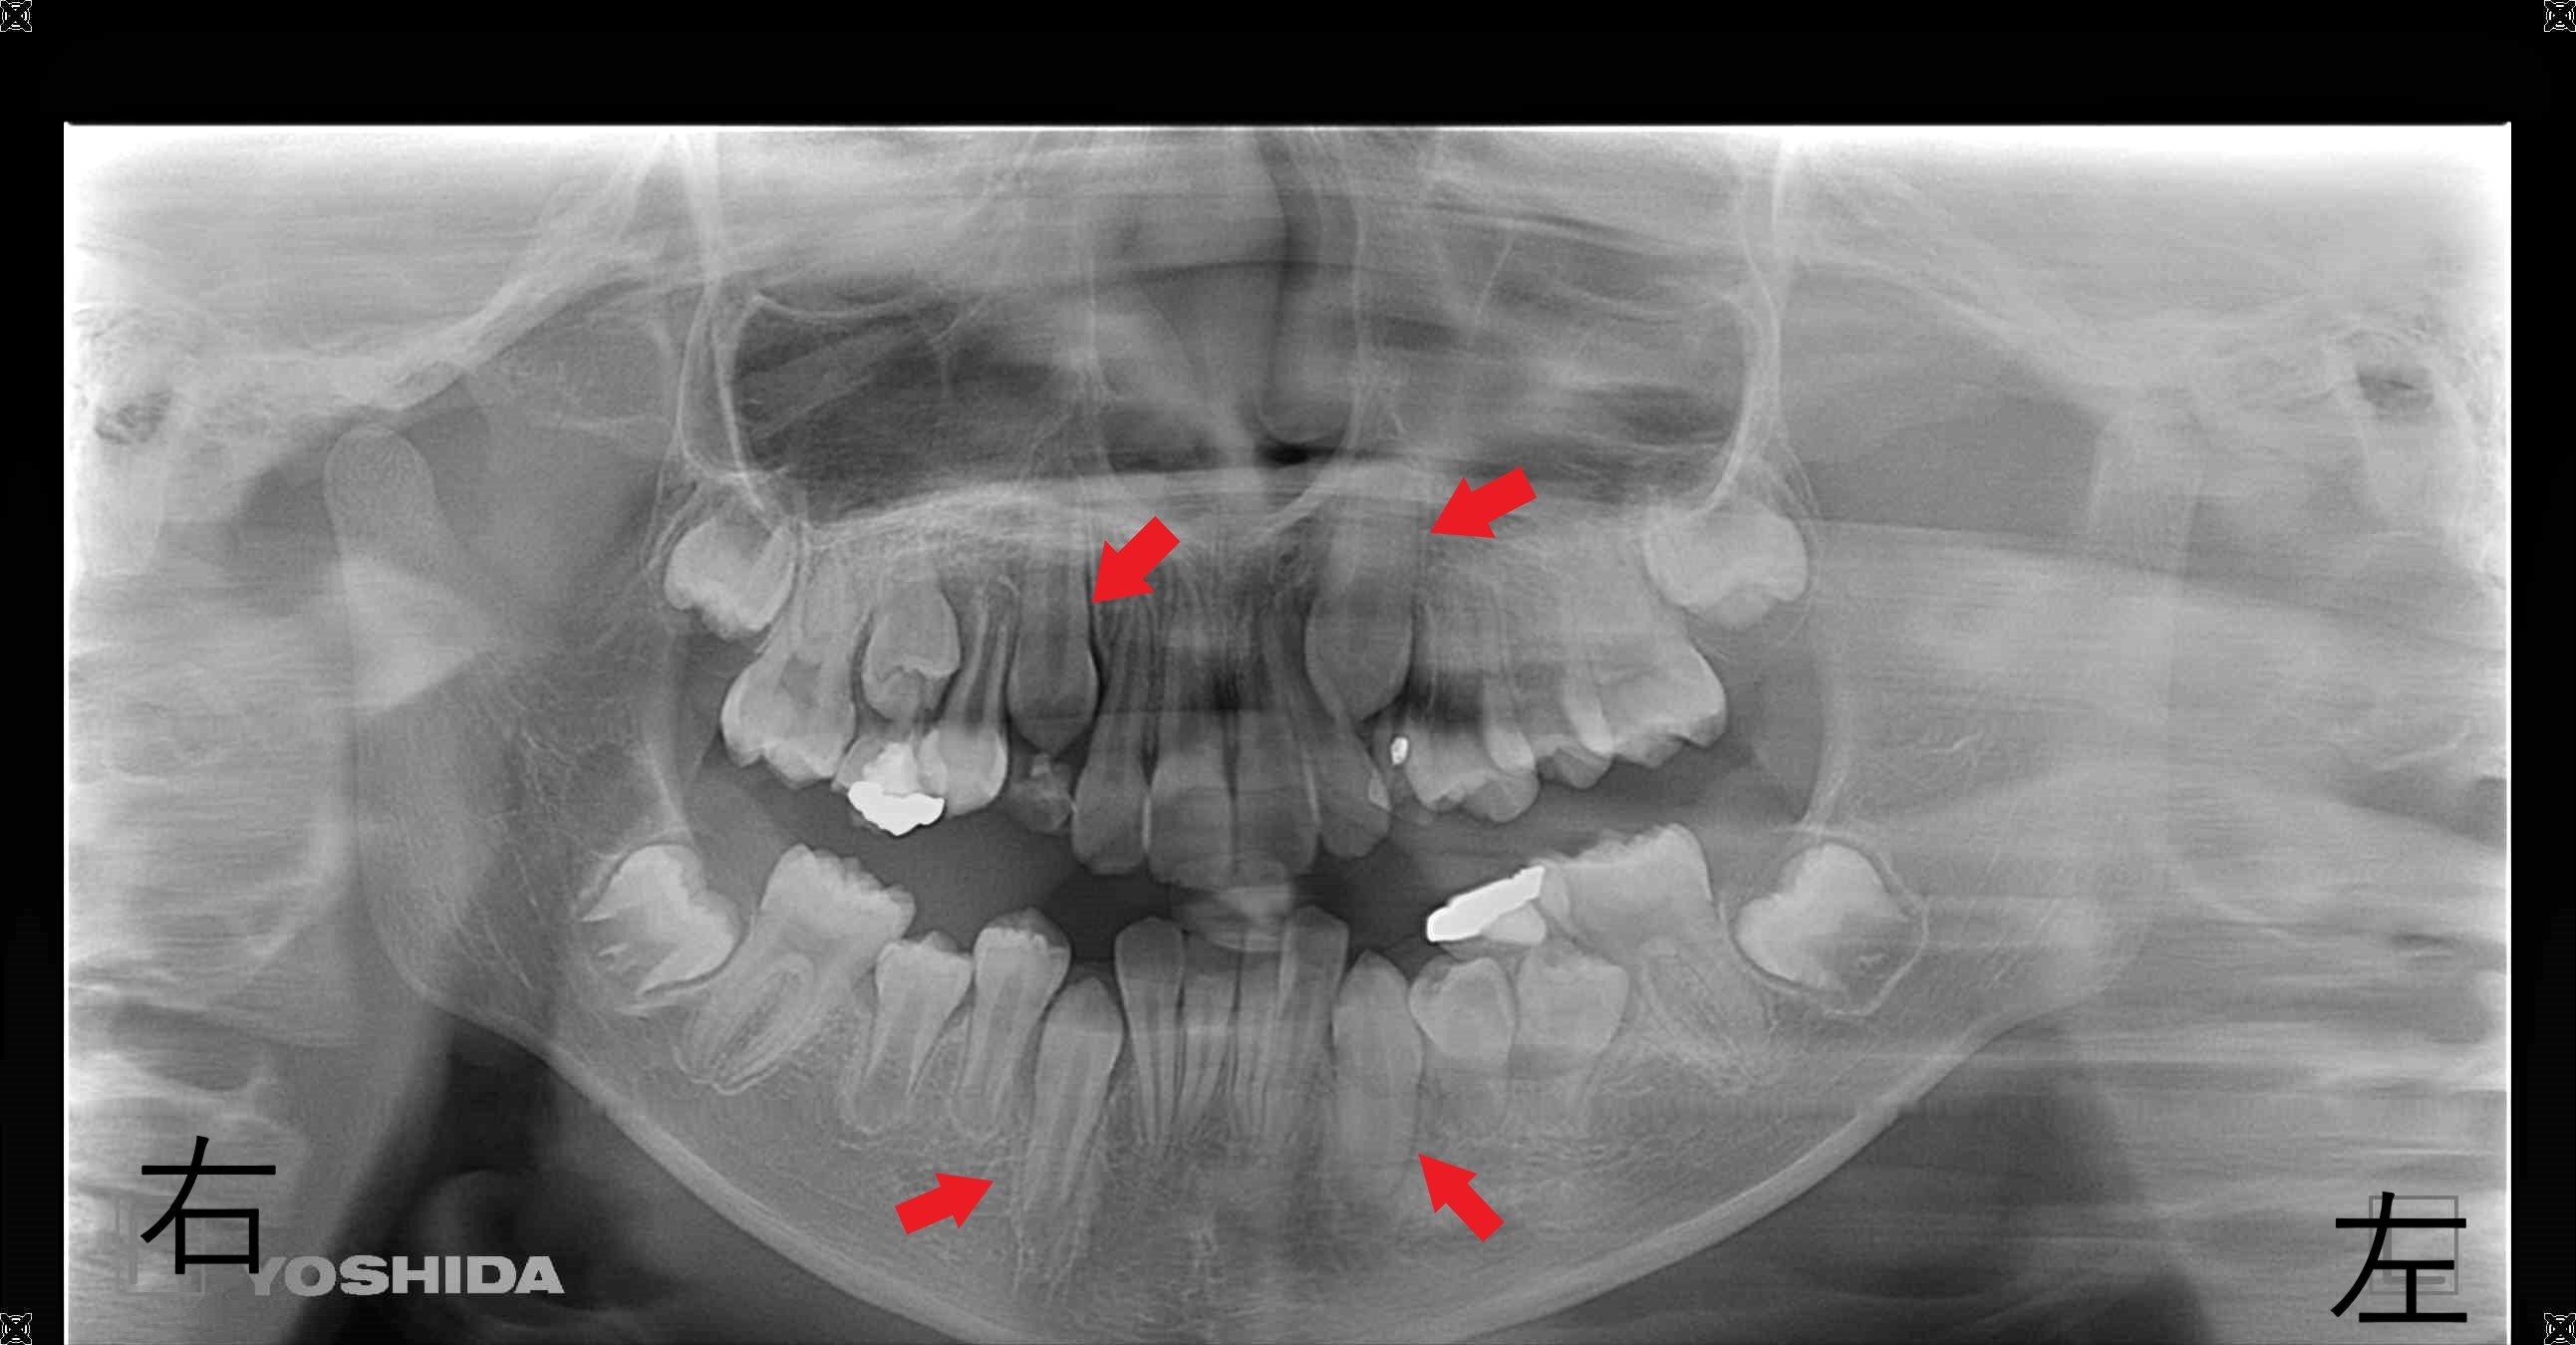

また、掲載のレントゲンでは、上下左右の犬歯の位置が確認できます。

下顎の犬歯はすでに萌出しており、上顎もまもなく萌出する状態でした。

この患者様は10歳6か月での治療開始となり、最適とされる時期より約2年後でした。

そのため、将来的にブラケットとワイヤーによる本格的な矯正治療が必要となる可能性もあることをご家族にご説明し、取り外し式装置(マイオブレイス)による治療を開始しました。